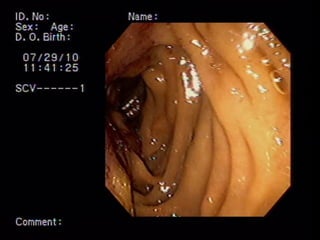

COLEDOCODUODENOSTOMIA

Coledocoantrostomia DRENAJE BILIAR ECOGUIADO

Coledocogastrostomia DRENAJE BILIAR ECOGUIADO